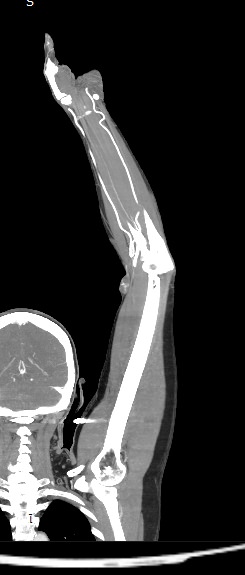

Мультиспиральная компьютерная томография сосудов верхних конечностей (КТ-ангиография) применяется для оценки состояния и функционирования артериальной сосудистой системы руки. При заболеваниях сосудов развивается нарушение кровообращения в руках, что проявляется симптомами ишемии верхних конечностей: боли в мышцах, онемение, бледность и похолодание пальцев рук.

КТ-ангиография позволяет увидеть анатомические особенности строения сосудов рук, выявить врожденные аномалии развития сосудов, диагностировать наличие аневризм, а также сужения просвета сосудов на фоне атеросклероза и других сосудистых заболеваний. КТ применяется в хирургической практике при планировании оперативных вмешательств и в последующем для оценки эффективности хирургического лечения.

В диагностических центрах «Доступная медицина» КТ-ангиография сосудов верхних конечностей проводится на современных мультиспиральных томографах последнего поколения TOSHIBA AQUILION. Аппараты послойно сканируют зону исследования, делая одновременно от 64 до 128 тончайших срезов области рук. Такая скоростная мультисрезовая методика сканирования обеспечивает высокое качество изображений при минимальной лучевой нагрузке на пациента.

При помощи инновационных компьютерных программ полученные при сканировании данные трансформируются в цифровые трехмерные изображения сосудистой системы. 3D-модели дают возможность увидеть пространственное взаимоотношение анатомических структур, что значительно повышает точность диагностики.